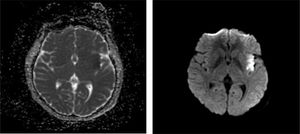

Caso clínicoUna mujer de 27 años, de profesión abogada, sin antecedentes médicos relevantes y sin síntomas de COVID, acudió al servicio de urgencias por cuadro clínico de inicio agudo, caracterizado por hemiparesia y hemihipoestesia derecha, enlentecimiento psicomotor y afasia no fluente. La tomografía cerebral en urgencias no evidenció alteraciones. Luego, se realizó una resonancia magnética cerebral, donde se observó lesión isquémica insular derecha (fig. 1). A las 48h, la paciente presentó mejoría de la hemiparesia y de la fluencia del lenguaje, persistiendo la hemihipoestesia derecha. Al quinto día se realizó valoración neuropsicológica intrahospitalaria, que evidenció compromiso en la memoria inmediata y diferida, la atención, el cálculo, el lenguaje y las capacidades visoconstructivas, objetivándose un bajo desempeño en el Mini-Mental (10 puntos) y en el Test del Reloj (4 puntos) (tabla 1). Se realizó una valoración semiológica de afasias que arrojó dificultades en la capacidad nominativa, la repetición y la fluencia del lenguaje, junto con automatismos y estereotipias verbales. Seguidamente, se administró el Test de Nominación de Boston, para el diagnóstico de la afasia, donde obtuvo 4 puntos, confirmando la afasia motora.

Lesión isquémica insular derecha en imagen de secuencia de difusión ponderada (DWI) y mapa del coeficiente de difusión aparente (ADC). Imagen de resonancia magnética que muestra una lesión en la región insular. A la derecha, DWI que evidencia una hiperintensidad focal en el ribete insular, indicativa de isquemia aguda. A la izquierda, ADC que revela una hipodensidad compatible con restricción a la difusión, confirmando el diagnóstico.